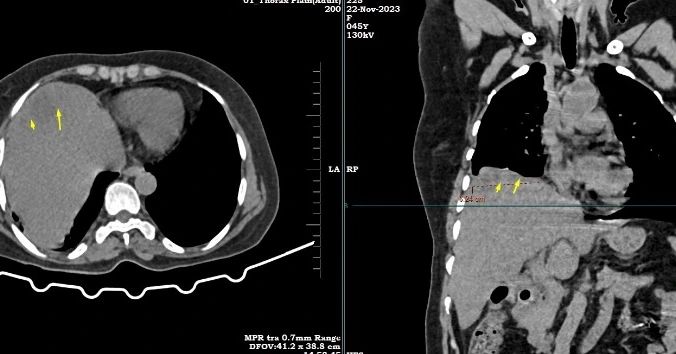

Mild elevation of right dome of diaphragm with evidence of approximately 6 x 7.5 x 2.7 cm right subphrenic low attenuation collection (evaluation is limited due to lack of IV contrast study) – *likely suggestive of subphrenic abscess*

Trace right pleural effusion with subpleural atelectasis in posterior basal segment of right lower lobe.